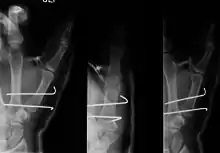

Bennett's fracture

Bennett fracture is a fracture of the base of the first metacarpal bone which extends into the carpometacarpal (CMC) joint.[1] This intra-articular fracture is the most common type of fracture of the thumb, and is nearly always accompanied by some degree of subluxation or frank dislocation of the carpometacarpal joint.

- For Bennett fractures where there is between 1 mm and 3 mm of displacement at the trapeziometacarpal joint, closed reduction and percutaneous pin fixation (CRPP) with Kirschner wires is often sufficient to ensure a satisfactory functional outcome. The wires are not employed to connect the two fracture fragments together, but rather to secure the first or second metacarpal to the trapezium.

- For Bennett fractures where there is more than 3 mm of displacement at the trapeziometacarpal joint, open reduction and internal fixation (ORIF) is typically recommended.